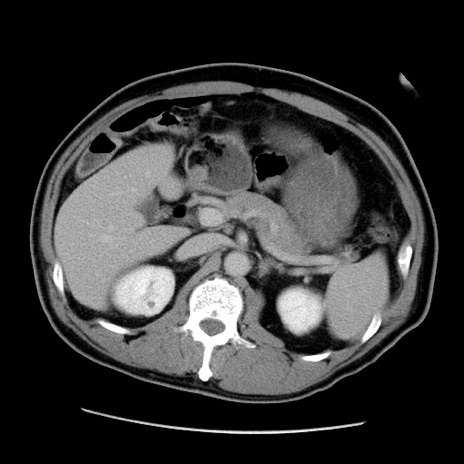

冠状断像

【症例】50歳代男性

【主訴】腹痛

【現病歴】AVMからの被殻出血のため回復期リハ病棟入院中。 本日午後3時頃急に下腹部痛が出現した。

【既往歴】AVM、被殻出血、虫垂炎、高血圧

【身体所見】意識晴明、左半身不全麻痺、会話の理解は良好、36.5°C、腹部:膨隆、全体に板状硬、下腹部正中に圧痛点あり、反跳痛-、筋性防御不明、右下腹部にope scar

【データ】WBC 9400、CRP 0.06